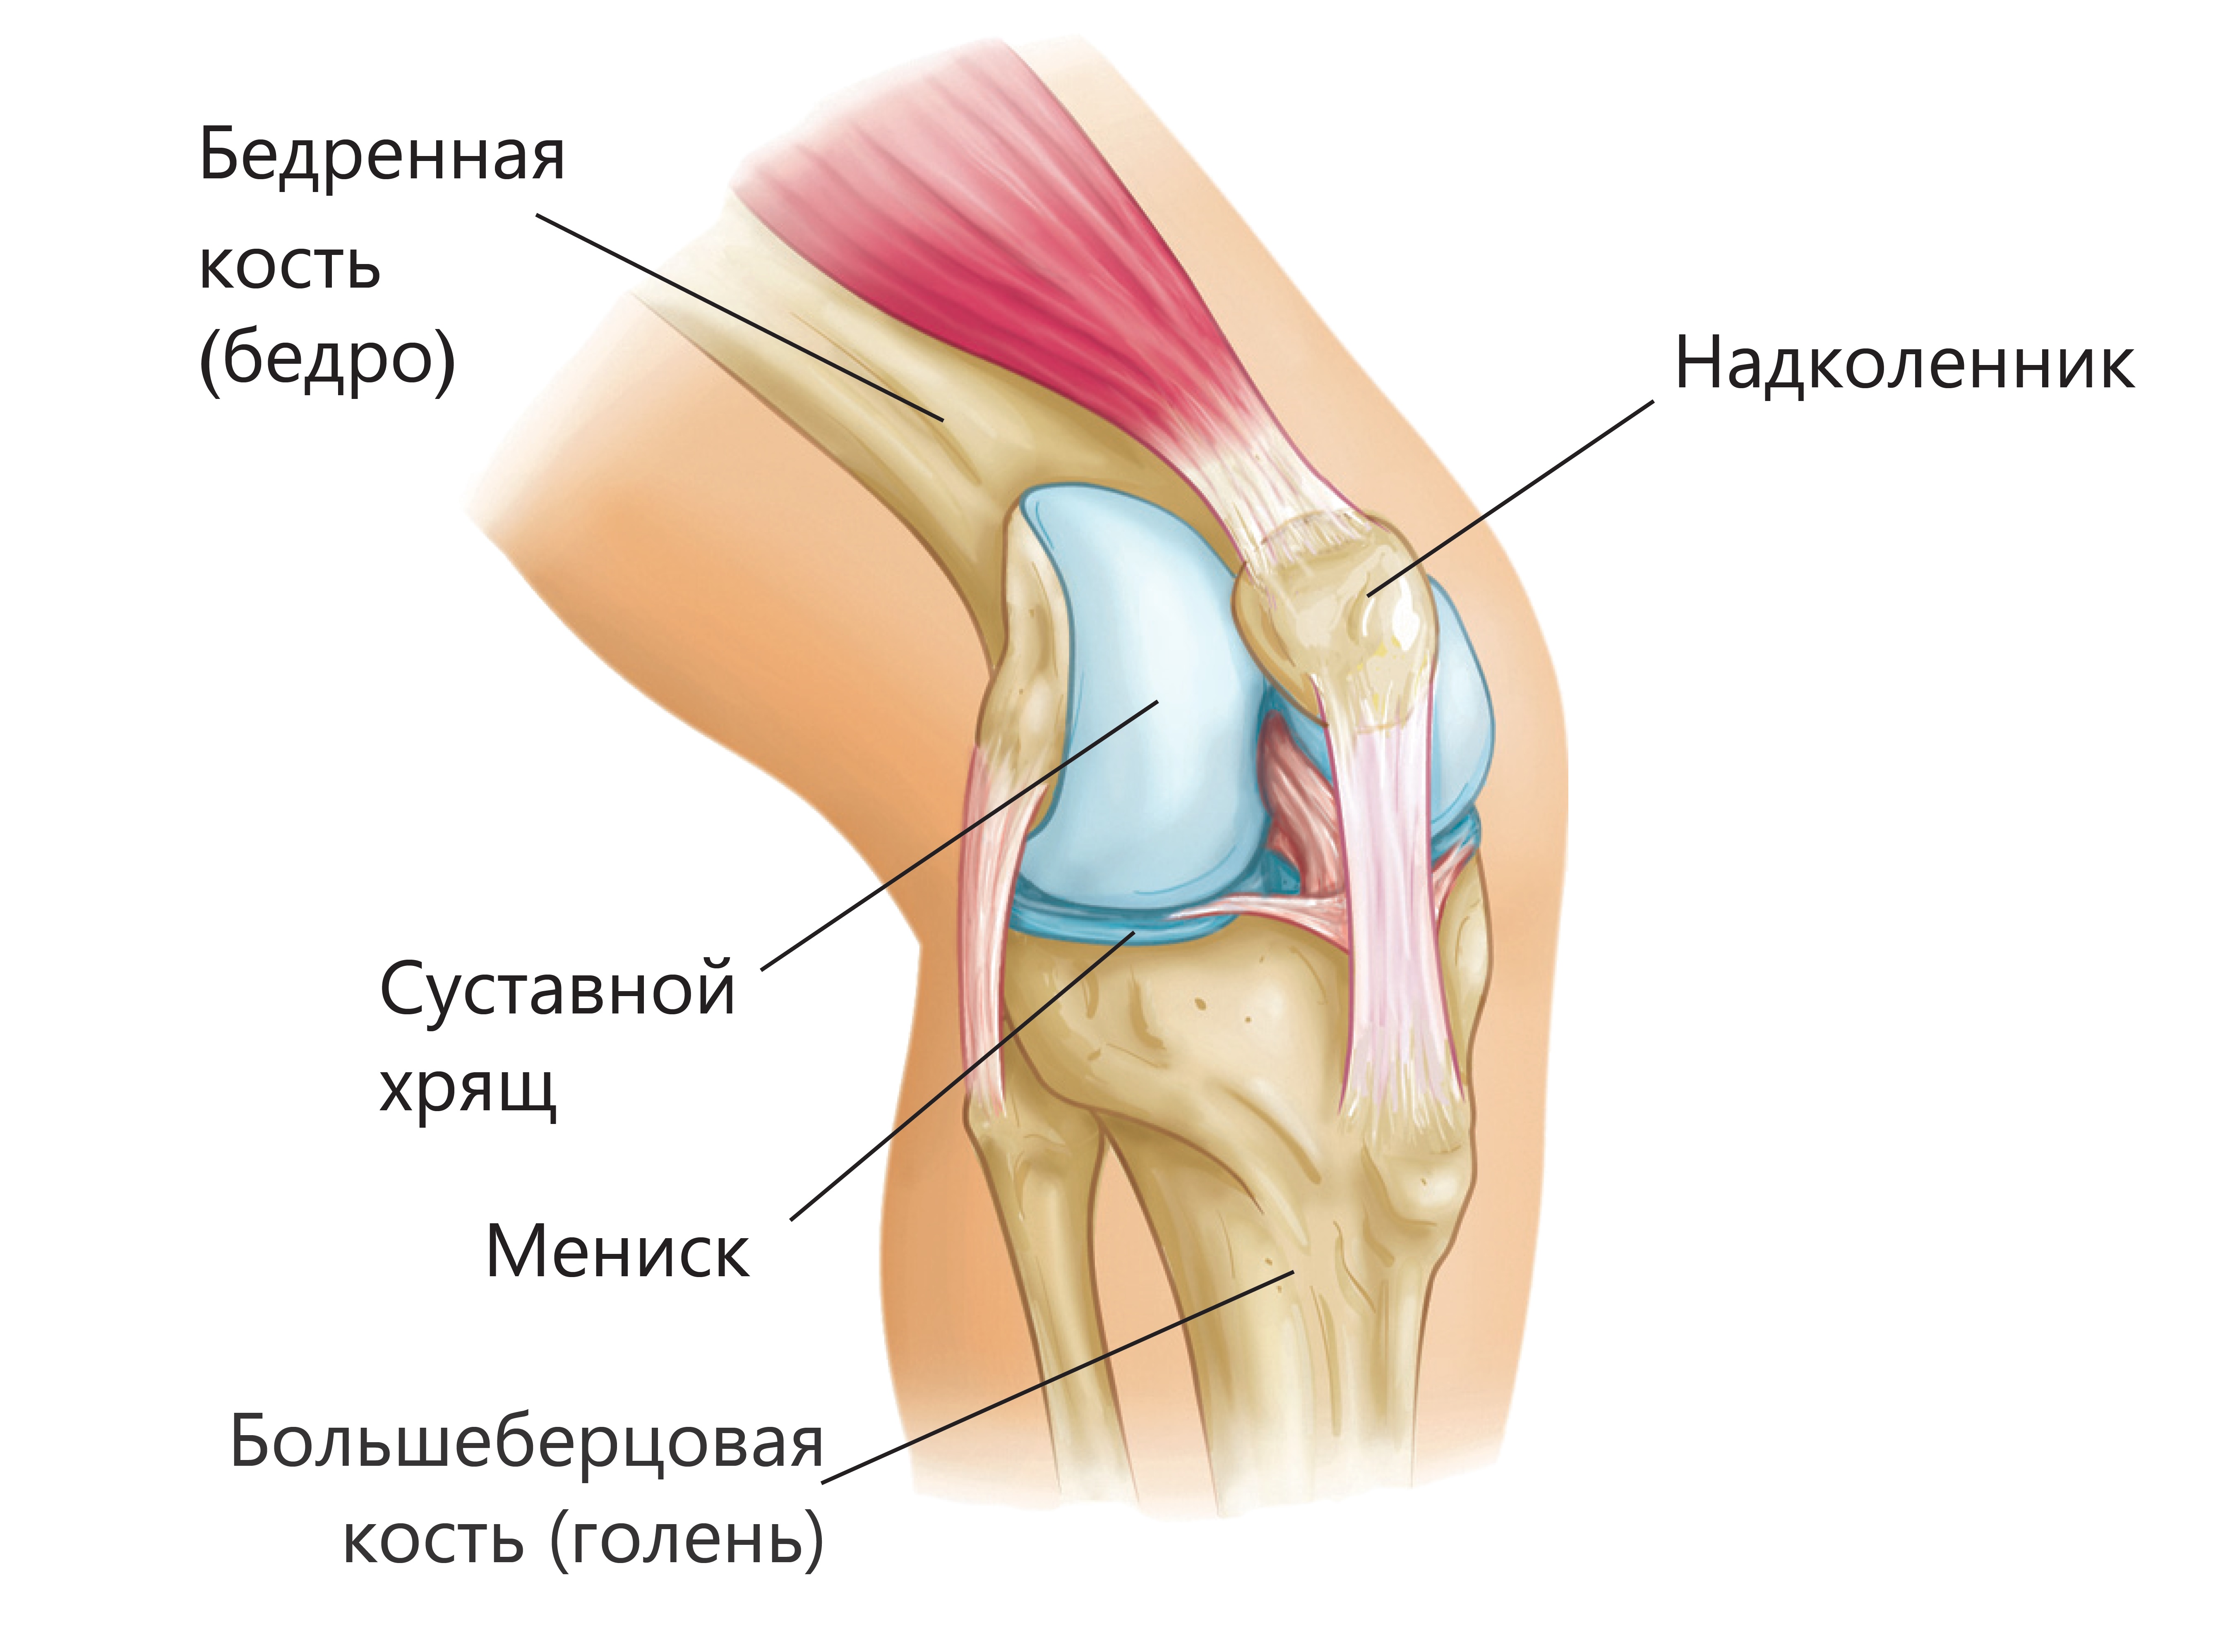

Анатомия коленного сустава: изучение анзерита и его влияния